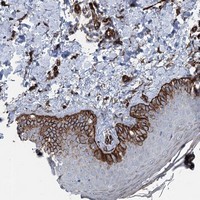

- Immunohistochemical staining of human skin with IQSEC1 polyclonal antibody (Cat # PAB23229) shows strong cytoplasmic positivity in basal cells of squamous epitheium at 1:50-1:200 dilution.

- Immunohistochemistry (Formalin/PFA-fixed paraffin-embedded sections)